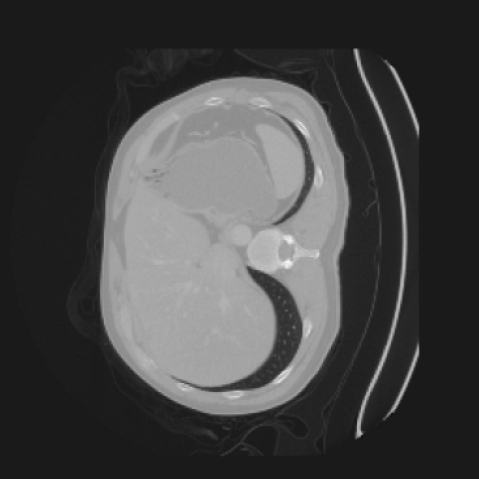

As shown in Figure 5, the generated slices exhibit high consistency across adjacent slices. The anatomical structures and semantic patterns are smoothly and coherently preserved between slices, indicating that our model is capable of generating 3D-consistent synthetic images rather than isolated 2D slices.

In our approach, we employ a compression factor of 4 to encode 3D medical images into the latent space. This level of compression reduces the spatial resolution of the original image (e.g., from 256×256 to 64×64 per slice), while still preserving the essential anatomical structures and semantic content. The latent representation at this scale offers a favorable trade-off between dimensionality reduction and semantic fidelity. Specifically, although fine-grained textures are simplified, key structural patterns (e.g., organ boundaries, lesion shapes) remain visually distinguishable and semantically coherent. As the compression rate increases, the latent representations become progressively more abstract. With lower compression (e.g., 2× or 4×), the latent features preserve key anatomical structures and spatial layouts, making them beneficial for our semantic image synthesis task in latent space, as the model can operate on compressed representations that retain sufficient semantic information without being overwhelmed by high-frequency noise. In contrast, higher compression rates (e.g., 8× or above) lead to a loss of fine-grained details and reduced semantic fidelity. The choice of a 4× compression thus ensures that the latent features are compact and meaningful, facilitating effective conditional generation while significantly reducing computational overhead. We therefore adopt a 4× compression as a compromise between computational efficiency and semantic preservation. The corresponding 2D slices in image space and latent space are shown in Figure 7.